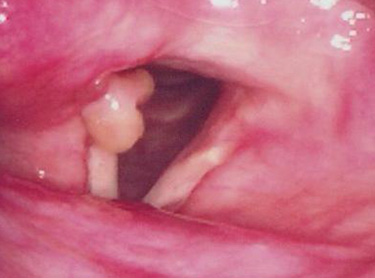

A granuloma can be classified into two types; contact granuloma and intubation granuloma. Main symptom is the infection on the membrane and cartilage web around the vocal process and this can form a granuloma as a result of laryngopharyngeal reflux.

There are two types of granuloma which are contact granuloma and intubation granuloma.

Contact granuloma can be caused by voice abuse, chronic cough, habitual cough or laryngopharyngeal reflux.

This is usually found in men and the main symptoms are pain and foreign-body-sensation in the throat.

Intubation granuloma is often caused after a laryngeal surgery, bronchoscope test, or endotracheal intubation.

At the beginning, the granuloma becomes larger in size, but after certain days, it starts to degenerate.

In many cases, the granuloma comes bilaterally, and hoarseness is not severe. It is usually found in females.